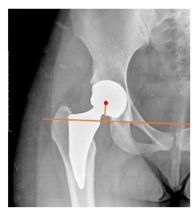

Plain radiographs were evaluated preoperatively and at the most recent follow-up, after appropriate calibration. Positional parameters were assessed according to values guidelines from published literature, as listed in Table 1 [23,24,25,26,27,28,29,30,31]. Femoral stem and acetabular cup osteointegration were quantified according to Engh [32] and Moore scale [33]. Heterotopic ossifications were graded according to the Brooker system [34].

3.4. Radiographic Evaluation

Preoperative and postoperative radiographic data are reported in Table 4. Preoperatively, 18 THR (24.3%) were implanted in skeletally immature children with closed triradiate cartilage (1 ≤ Risser ≤ 3). Radiographic acetabular insufficiency (LCEA < 25° and AI > 13°) was detected in 14 hips (18.9%), while protrusion was present in 3 hips (4.1%) An excessive valgus of the femoral neck was observed in 19 hips (25.7%), while an important varus deformity was present in 7 hips (9.5%).

Postoperative radiographs showed a significant vertical malposition of the cup in 1 case (1.4%), a significant varus stem in 8 cases (10.8%) and a significant valgus stem in 1 case (1.4%). Two patients (2.7%) showed moderate heterotopic bone formation (Brooker ≥ 2), that did not significantly affect the hip motion and symptoms. All those THR that did not undergo revision showed good radiographic osteointegration, with no evidence of implant breakage, radiographic lucencies, bone defects, cup migration, or stem subsidence at the most recent radiographs.

In our experience, implant malposition was the only reason for implant revision. In one case, progressive subsidence was observed in a varus undersized stem, implanted in a boy with Albers–Schömberg disease; in another case, an excessively vertical cup with a 28 mm femoral head caused hip instability and required cup revision.

THR can be a challenging procedure in very young people. The combination of distorted anatomy, small physique, and poor bone stock can impede proper implant placement. Implant sizing may be an issue in these patients. The combination of young age and peculiar conditions such as skeletal dysplasia may require particular attention in preoperative planning and implant selection. Noticeably, we used the smallest size of the cup in 11 hips (15%) and the smallest size of the stem in 14 hips (19%). A meticulous preoperative planning, even using simulation software, [40,41,42] and careful implant selection, sometimes requiring even customized implants [37], is crucial in such conditions, to prevent unpleasant pitfalls during the operation.